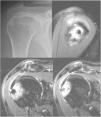

Caso clínico 2Mujer de 50 años, que consulta por un dolor en el hombro derecho (miembro dominante) de años de evolución y con el diagnóstico previo de tendinitis calcificante de hombro. Previamente a la consulta en nuestro centro había sido tratada mediante 6 sesiones de ondas de choque (3-4 años antes), una punción-aspiración ecoguiada (2 años antes) y numerosas sesiones de fisioterapia. En la exploración física la paciente presenta un balance articular completo tanto pasivo como activo, pero doloroso. Además presenta maniobras de provocación subacromiales dolorosas y dolor en la cara lateral del hombro, siendo el resto de la exploración normal. En la radiografía simple se observa una lesión nodular calcificada y esclerosa a nivel del troquíter que erosiona la cortical así como pequeñas calcificaciones en el espacio subacromial (fig. 4). En los estudios previos de la paciente, las calcificaciones ya estaban presentes, pero la lesión esclerosa ha aparecido tras los últimos tratamientos. Ante la sospecha clínica de tendinitis calcificante de hombro, se solicita una RM (fig. 4). Se realiza un TAC para delimitar la extensión y valorar la posible reacción perióstica (fig. 5).

Radiografía simple de hombro, proyección anteroposterior: se observa una lesión nodular calcificada y esclerosa a nivel del troquíter que erosiona la cortical así como pequeñas calcificaciones en el espacio subacromial (imagen superior izquierda). Imágenes de RM: se confirman las calcificaciones en el tendón del supraespinoso y se observa una lesión nodular de 6mm en el troquíter, hipointenso en todas las secuencias, que erosiona la cortical y se asocia con importante edema óseo circundante (imágenes superior derecha, inferior izquierda e inferior derecha).